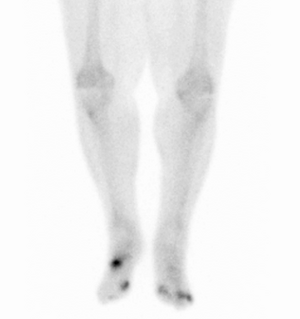

Nuclear medicine scans can be a helpful adjunct to MRI in patients who have metallic hardware that limits or prevents effective magnetic resonance. Generally a triple phase technetium 99 based scan will show increased uptake on all three phases. Gallium scans are 100% sensitive for osteomyelitis but not specific, and may be helpful in patients with metallic prostheses. Combined WBC imaging with marrow studies has 90% accuracy in diagnosing osteomyelitis.[26]